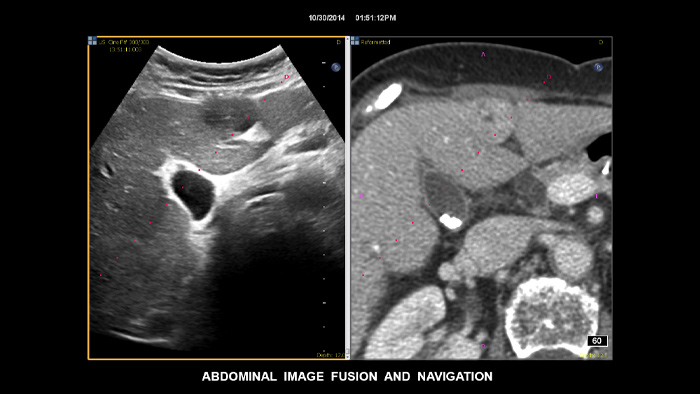

Treffen Sie auch in diagnostisch schwierigen Fällen die richtige Entscheidung mit den Philips Funktionen zur Bildfusion und Nadelnavigation. Ein effizienter Arbeitsablauf ermöglicht Klinikteams eine schnelle und effektive Fusion von CT/MRT/PET mit Live-Ultraschallbildern, wobei die Nadelnavigation die Biopsieführung bei kleinen, schwer zugänglichen Läsionen unterstützt.³

Mit der Tumorkontur können Anwender Läsionen mit einem halbautomatischen Tool planen und hervorheben. Es erleichtert das Zeichnen einer 3D-Kontur um die relevante Struktur und bietet so Unterstützung in schwierigen Fällen, bei denen die Läsion nicht einfach zu erkennen ist.